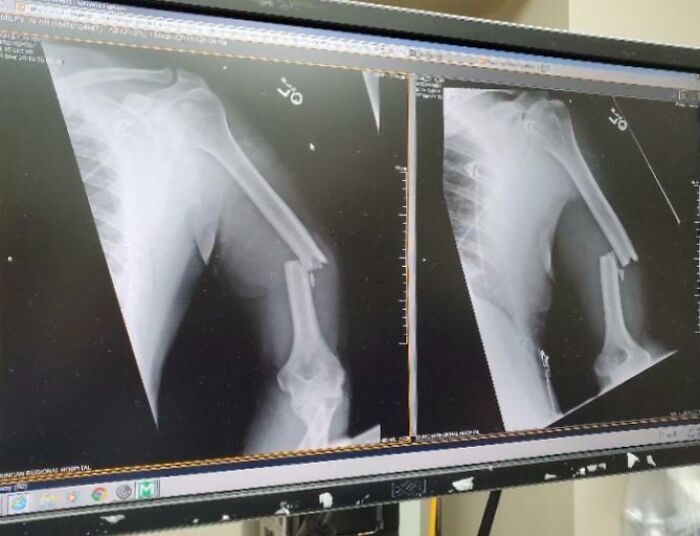

#7 Ruka môjho (takmer 60-ročného) otca po tom, čo do neho dnes ráno narazila krava